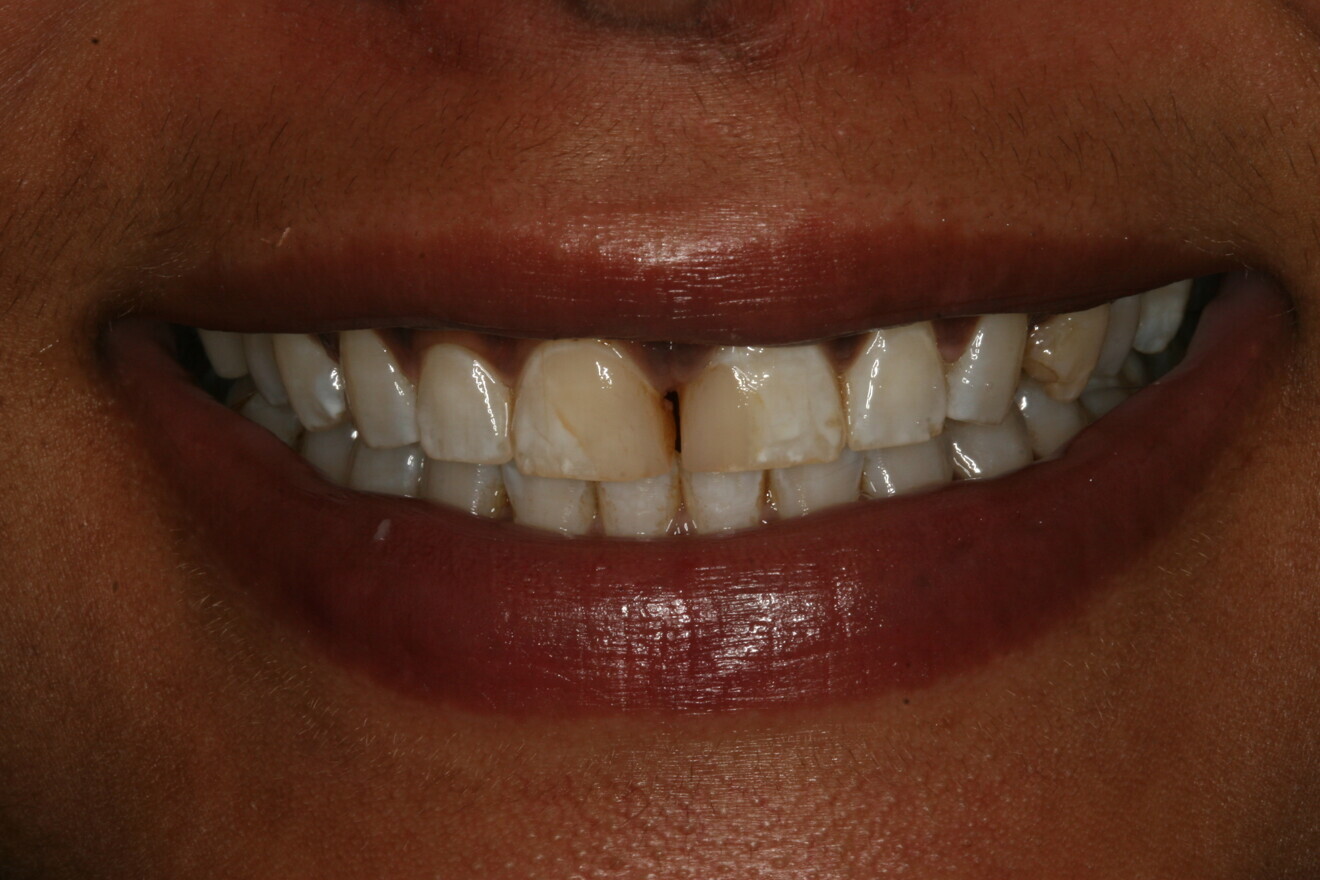

The 24-hour post­operative check ap­pointment was particularly important because it allowed the patient to express feedback based on self-analysis of the proposed shapes and contours of her new smile. The patient reviewed and ap­proved the shape of her provisional res­torations and the shade tabs selected at the prior appointment. Proper phonetics, occlusion and anterior guidance were confirmed. A few minor adjustments to her occlusion on the lingual aspect of the provisional res­torations were required. Photographs of the approved provisional restorations and shade tabs were taken (Figs. 4–6). Other provisional records were taken, in­cluding a Futar D stick bite in centric occlu­sion and a Honigum Pro im­pression of the approved provisional restorations (Fig. 7). All the records were disinfected and sent to the ceramist, accompanied by a completed laboratory prescription, notes and all the photographs taken to that point. The ceramist was instructed to use the impression of the approved provisional res­torations as a guide for the final shape, size and contour of the porcelain restorations.

Fig. 6: Full-face view of the approved provisional restorations.